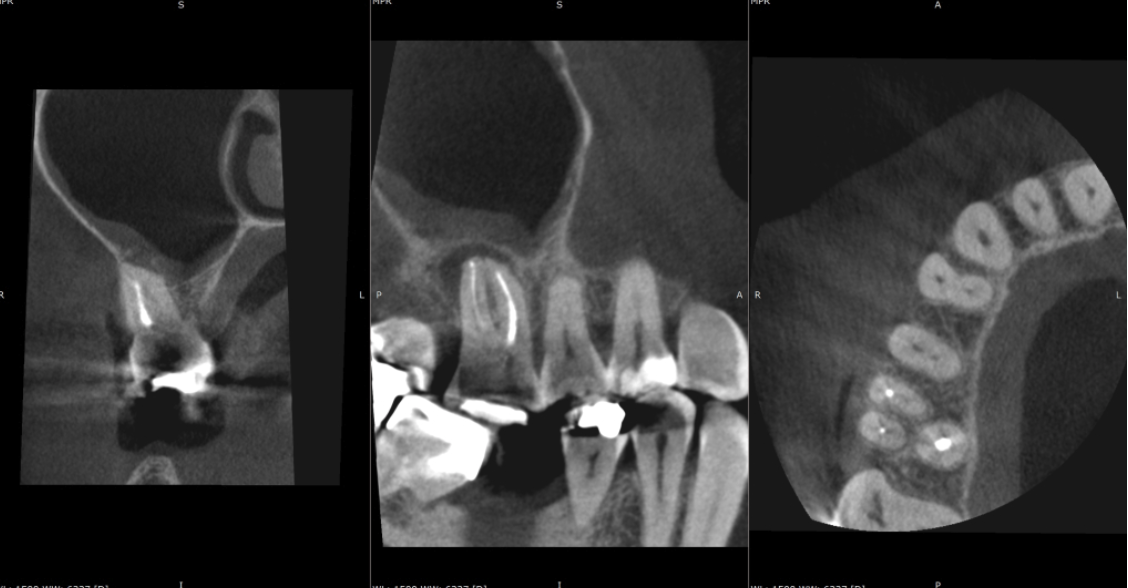

Key findings from CBCT Consultant radiologist’s report by JM Radiology:

- No evidence of a fractured file in the mesial root.

- Vertucci type VI 2-1-2 canal configuration in the mesial root (5-20% of upper first molars are thought to have this canal configuration which is potentially high, so we need to be on the lookout for it!)

- Unfilled mb2 canal

- No signs of PAP on the palatal root (this information became relevant as the treatment progressed)

The information provided by the CBCT made the management of this case far more predictable and allowed me to plan a strategy that would best suit this tooth’s anatomy. This treatment was completed over 2 visits (each visit approximately 90 minutes long). A caries-led access uncovered cracks in the mesial and distal walls that extended into the pulp chamber but stopped before crossing the base of the tooth. Follow the link below for the latest guidance on the endodontic management of cracked teeth (https://onlinelibrary.wiley.com/doi/full/10.1111/iej.14186).